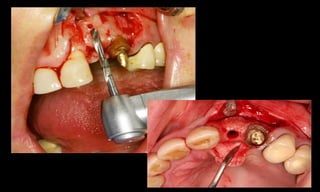

10-10-2005

Novembro de 2005

24-01-2006

Cone Morse